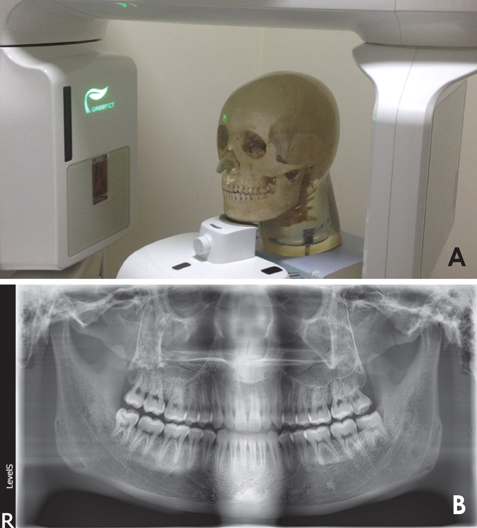

牙科細節(jié)頭部模型專用于牙科X線設備而設計,如:全景牙科,頭頜面攝影,牙科錐束CT,或一般三維成像應用

模型具有一個真正的人類頭蓋骨與下頜骨及五節(jié)頸椎,頜骨略微張開。 由于齒列完整的嵌入到組織等效材料中,因此體模不能與用于訓練或測試的口腔內傳感器一起使用。

對于牙科X光檢查中的偽影評估,包括牙齒修復或嵌體??梢愿鶕?jù)客戶要求添加特定的牙齒修復,材料填充或牙冠。

在三腳架上用一個M6螺絲孔就可以快速方便定位模型。

B.法蘭克福標準平面-全景牙科攝片

人類頭蓋骨與下頜骨及五節(jié)頸椎